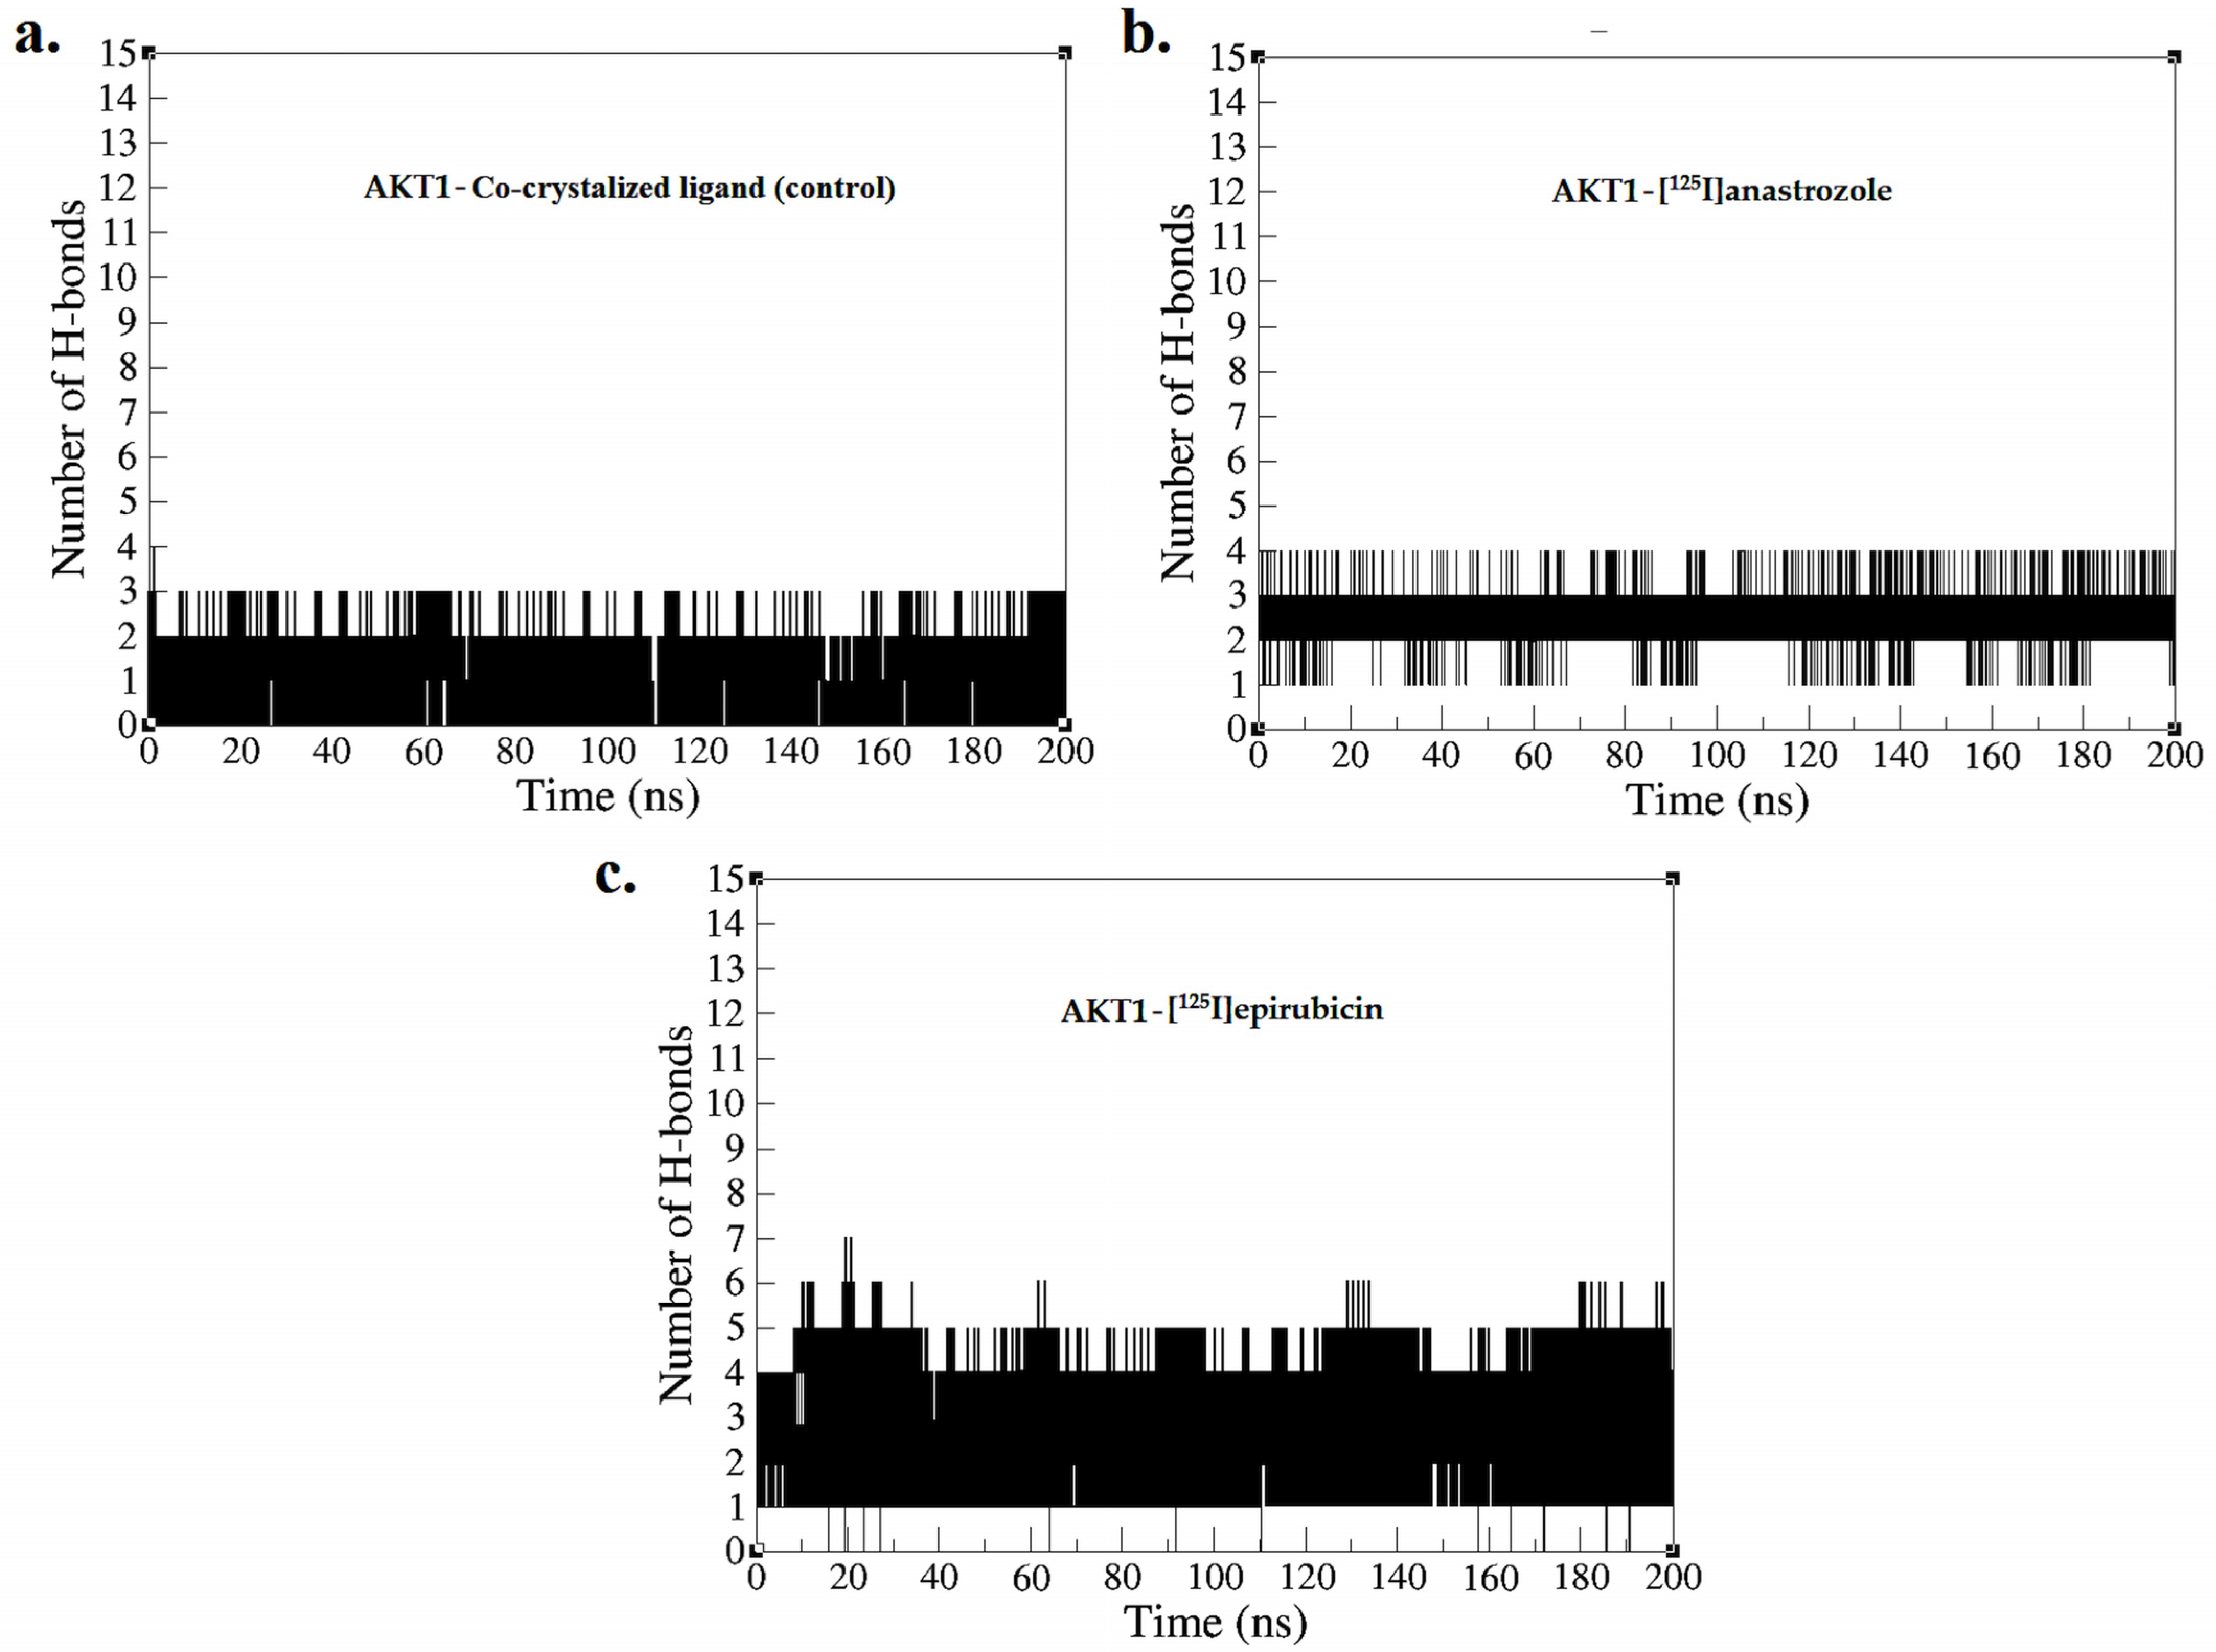

2.2. Molecular Dynamic Simulation

3.2. Molecular Dynamic Simulation

4.2. Molecular Dynamic Simulation